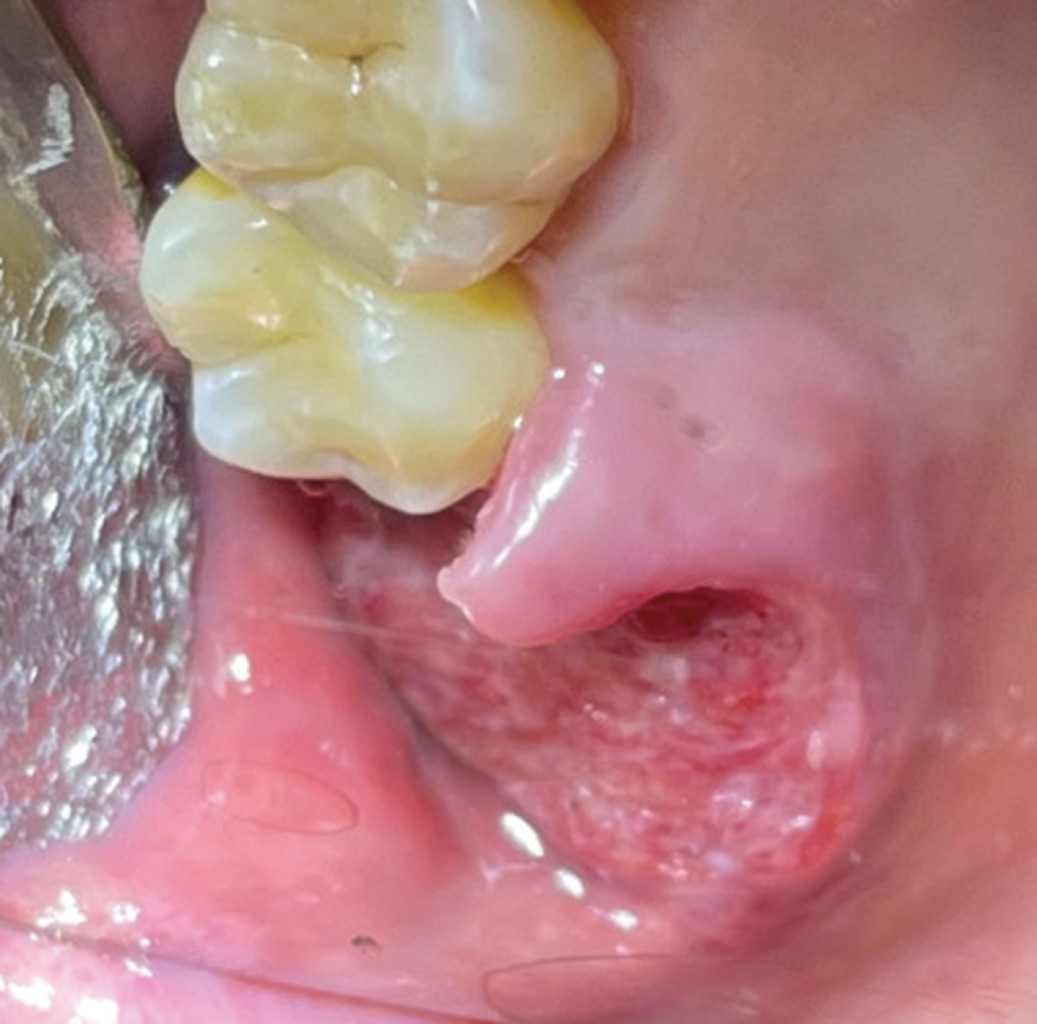

Se reciben dos fragmentos de tejido blando fijado en formalina, de forma y superficie irregular, consistencia firme, color café claro, que miden en conjunto 3.5 × 1.5 × 1.0 cm. Se realiza corte longitudinal y se incluye en su totalidad (Figura 4).

El espécimen está formado por islas de epitelio escamoso estratificado con displasia severa que infiltra el tejido conectivo fibroso denso, bien vascularizado disqueratosis, con infiltrado inflamatorio crónico leve difuso, hemorragia reciente, glándulas salivales mucosas, conductos estriados, músculo estriado. Revestido por epitelio escamoso estratificado paraqueratinizado con edema intracelular y solución de continuidad con fibrina e infiltrado inflamatorio mixto severo difuso. No presenta bordes sanos (Figura 5).